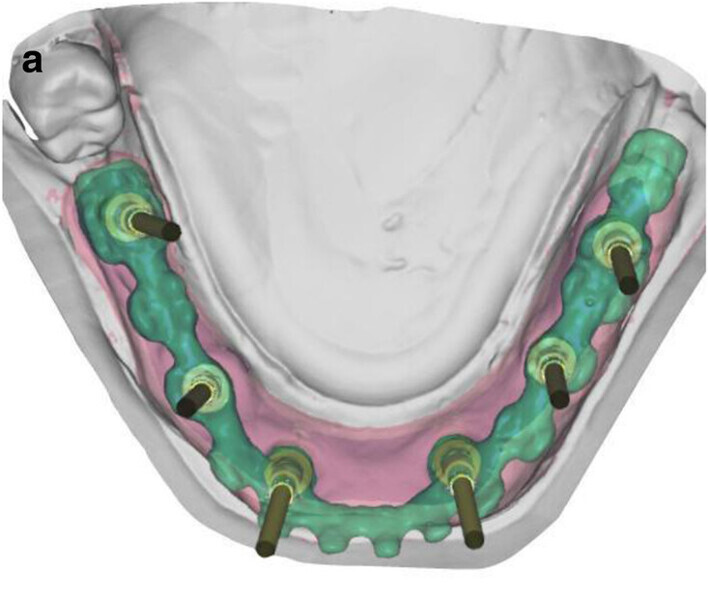

Fig. 5a: CAD/

CAM-fabricated surgical guides: tooth- and mucosa- supported (a) and implant- and mucosa-supported (b).

Fig. 5b: CAD/